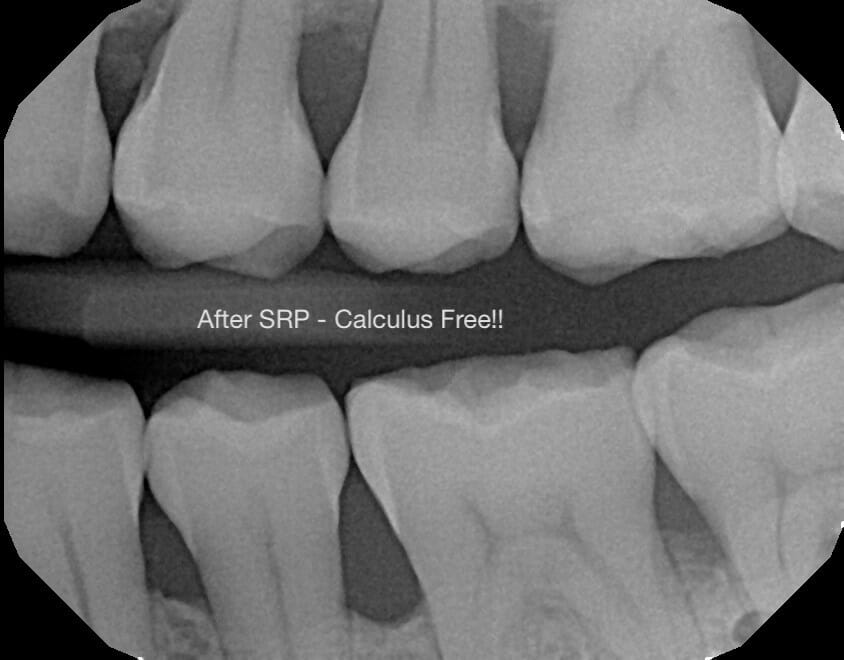

One of our two awesome hygienists (Ciera or Edith) will remove the bacteria from underneath your gums. Once this is done, your gums will have a higher likelihood of shrinking back to a healthier, more stable, state.

This will also help to reduce or eliminate the bleeding you experience while brushing, while at the same time improving your overall gum tissue health – which will ultimately help to keep all of your current teeth present and in the correct place.

Unfortunately, the SRP procedure does not automatically restore your gums back to their original and pristine condition. This treatment is made to preserve and improve the gum tissue that remains. And while we can’t go back to the ole’ days, keeping the tissue you have and building on new healthy habits can make a drastic improvement. Additionally, we’ll prevent the progression of your gum disease – which is nice.